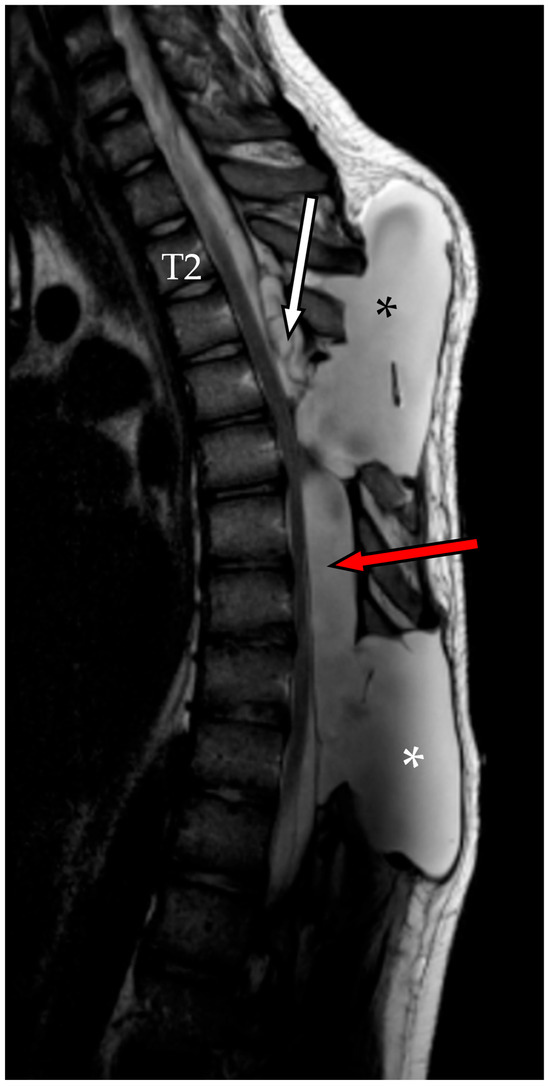

However, in early April, the patient returned to our emergency department with worsening of the bilateral lower limb weakness, gait disturbance, and urge incontinence. Neurological examination revealed bilateral leg weakness (M2 on the right, M3 on the left, globally), bilateral Babinski signs, and preserved perineal sensation. An emergent MRI was consistent with a further enlargement of the cyst and of the pseudomeningocele (Figure 5).

Figure 5. Emergent MRI, sagittal section, TSE T2-WI. Although the cranial component (red asterisk) remained stable, the caudal component (white asterisk), along with the pseudomeningocele (black asterisk), had enlarged and appeared under tension, which could explain the onset of the patient’s symptoms.